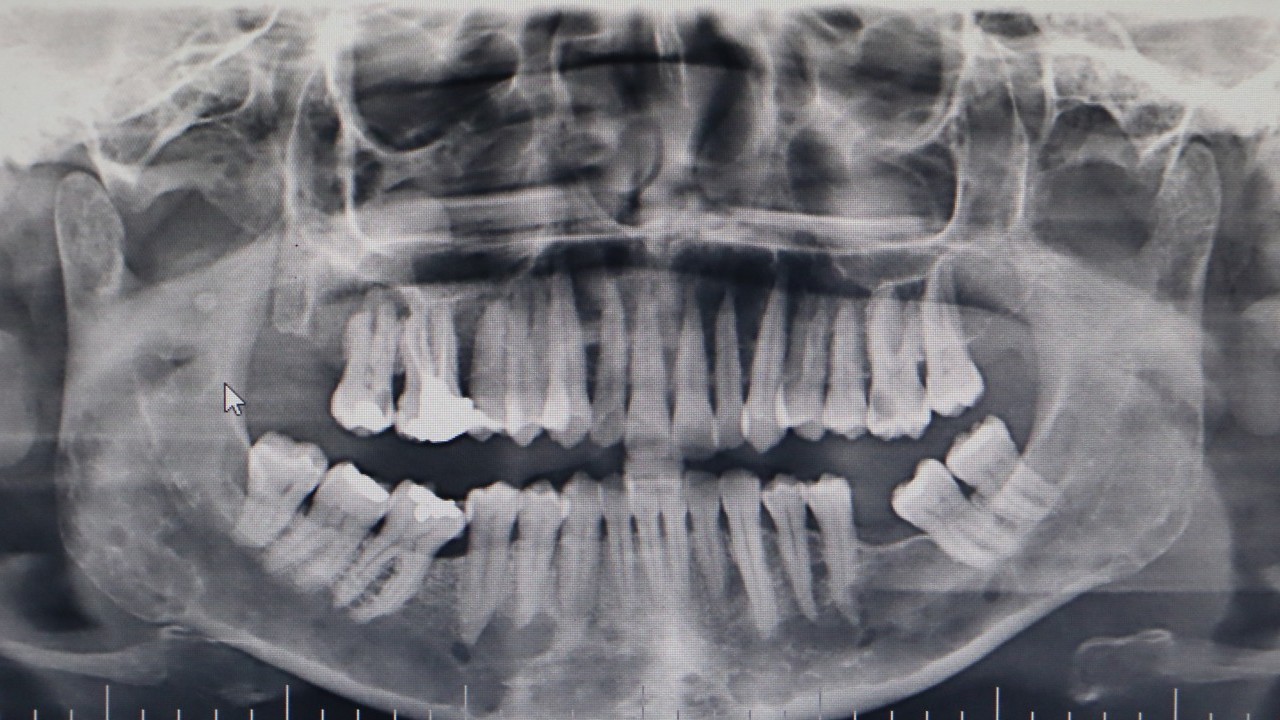

OMÜ Diş Hekimliği Fakültesi Dekanı Prof. Dr. Kaan Gündüz, vatandaşların ağız içi yaraları çoğu zaman önemsemediğini, tütün kullanımı, yetersiz ağız bakımı, güneş maruziyeti ve HPV virüsünün ağız kanserlerinin artışında etkili olduğunu ifade etti. Ağızda 2 haftadan uzun süren yaralar, sebepsiz diş sallanması, uyuşukluk ve çene ağrıları mutlaka dikkate alınması gerektiğini belirten Prof. Dr. Gündüz, ağız kanserinden korunma yolları arasında tütün ve alkol kullanımını azaltmak olduğunu belirtti. Prof. Dr. Gündüz, “Oral kanserler dediğimiz şey aslında başlangıçları çok hızlı ve sinsi gelişen durumlar. Bundan dolayı mutlaka hastaların 2 haftadan uzun süren ağızdaki yaraları eğer mevcutsa en yakın diş hekimlerine başvurmaları gerekmekte. En son yapılan, 2022 yılında Sağlık Bakanlığı yapmış oldu araştırmada 2 bin 246 tane ağız kanserine rastlanmış. Bu vakaların 551 tanesi ölümle sonuçlanmış. Bu da Türkiye kanser görülme olasılığını yüzde 1'ine tekabül ediyor ama şimdi şöyle bir durum var. Şimdi bizim insanlarımız kulağından bir damla kan gelince hemen işte gerekli doktora gider iken ağzından kan gelme durumunda çok fazla önemsemiyor. Yani ağız, dişler çok fazla önemsemiyor ne yazık ki. Ancak Özellikle son yıllarda artan tütün kullanımı ki bunun formasyonları var biliyorsunuz işte ne bileyim nargilesinden, piposundan, purosundan artmasından dolayı oral hijyenin, ağız bakımının eksikliğinden dolayı ve son yıllarda özellikle sizlerin de televizyonlarda veya işte bazı haber kanallarına duyduğunuz Human Papilloma Virüsü dediğimiz HPV'nin yaygınlaşmasından dolayı güneşe maruziyetinden dolayı insanlarda özellikle oral kanserler çok daha fazla sıklıkla görülüyor” diye konuştu.

ERKEN TANI HAYAT KURTARIYOR Ağız kanserinde erken tanı gerçekleşirse hastaların ölümle sonuçlanmasının önüne geçilebileceğini ifade eden Prof. Dr. Gündüz, “Biz kurum olarak Karadeniz'in en büyük üniversitesiyiz ve de fakülte olarak da Karadeniz'de büyük bir hizmet vermekteyiz. Ortalama yaklaşık günde 500 hasta, aylıkta 10 bine yakın hasta bakıyoruz. Biz yapmış olduğumuz seminerlerde hem öğrencilerimizi hem asistanlarımızı hem de halkımızı bu konuda bilgilendirmeye çalışıyoruz. Erken tanı eğer gerçekleşirse bu hastalıkların ölümle sonuçlanmasının nispeten önüne geçmiş oluyoruz. Çünkü erken tanı biliyorsunuz her kanser vakasında çok önemli bir yer tutmakta. Herhangi birisi ağzında eğer 2 haftanın üzerine geçmeyen bir yara varsa mutlaka en yakın diş hekimine başvurması gerekmekte.

Sebepsiz yere dişlerin sallanması, uyuşukluk olması, yüzde sebepsiz ağrıların, çene bölgesinde sebepsiz ağrıların oluşması kanserlerin başlangıç bulguları arasındadır. Zaten kanserlerin en fazla oluştuğu yerler ağız içerisinde dilin özellikle arka kenarlarıdır. Bunlar ne yazık ki başlangıçları da ağrısız olduğu için bir kısmının gözden kaçabilmekte. O yüzden insanlarımızdan, halkımızdan bu konuda dikkat etmeleri, eğer böyle bir lezyonla muhatap olurlarsa mesela bir yakınından ağız içerisindeki görüntüsünü çekmesini talep etmeli. 2 hafta sonra da aynı şekilde bu görüntü duruyorsa veya daha da büyümüşse en yakın merkeze gitmesini önermekteyiz” ifadelerini kullandı.